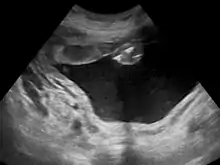

Polyhydramnios is a medical condition describing an excess of amniotic fluid in the amniotic sac. It is seen in about 1% of pregnancies.[1][2][3] It is typically diagnosed when the amniotic fluid index (AFI) is greater than 24 cm.[4][5] There are two clinical varieties of polyhydramnios: chronic polyhydramnios where excess amniotic fluid accumulates gradually, and acute polyhydramnios where excess amniotic fluid collects rapidly.

Diagnosis

During the pregnancy, certain clinical signs may suggest polyhydramnios. In the mother, the physician may observe increased abdominal size out of proportion for her weight gain and gestation age, uterine size that outpaces gestational age, shiny skin with stria (seen mostly in severe polyhydramnios), dyspnea, and chest heaviness. When examining the fetus, faint fetal heart sounds are also an important clinical sign of this condition.